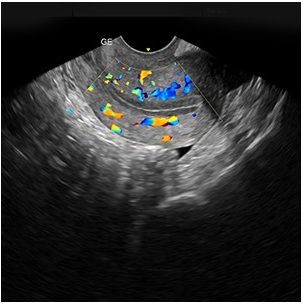

Our Endometrial Thickness Scan examines the lining of the womb to assess its suitability for implantation. This scan is specifically designed for those undergoing fertility treatment.